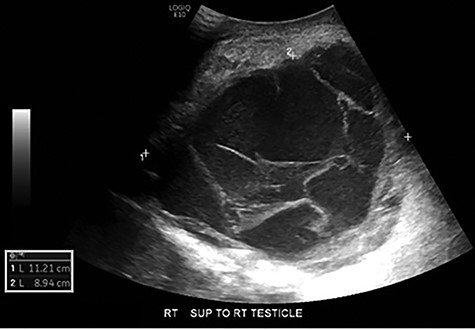

Scrotal ultrasonography revealed a complex septated cystic lesion on the right side of the scrotum (11.2 x 8.9 x 11.6 cm) (Fig. 1). The CT scan showed a large, complex solid and cystic mass (12.0 x 15.55 x 19.0 cm) in the right scrotum; and external to the testicle, a large amount of fat, with no abdominal lymphadenopathies (Fig. 2).

Scrotal ultrasound: complex septated cystic lesion on the right side of the scrotum measuring 11.2 x 8.9 x 11.6 cm. Nonspecific scrotal wall thickening was noted.